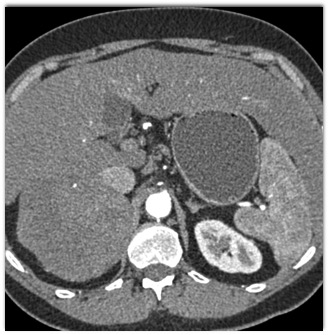

Based on CT findings the most likely diagnosis is?

pheochromocytoma

primary adrenal carcinoma

metastatic melanoma

adrenal cortical adenoma